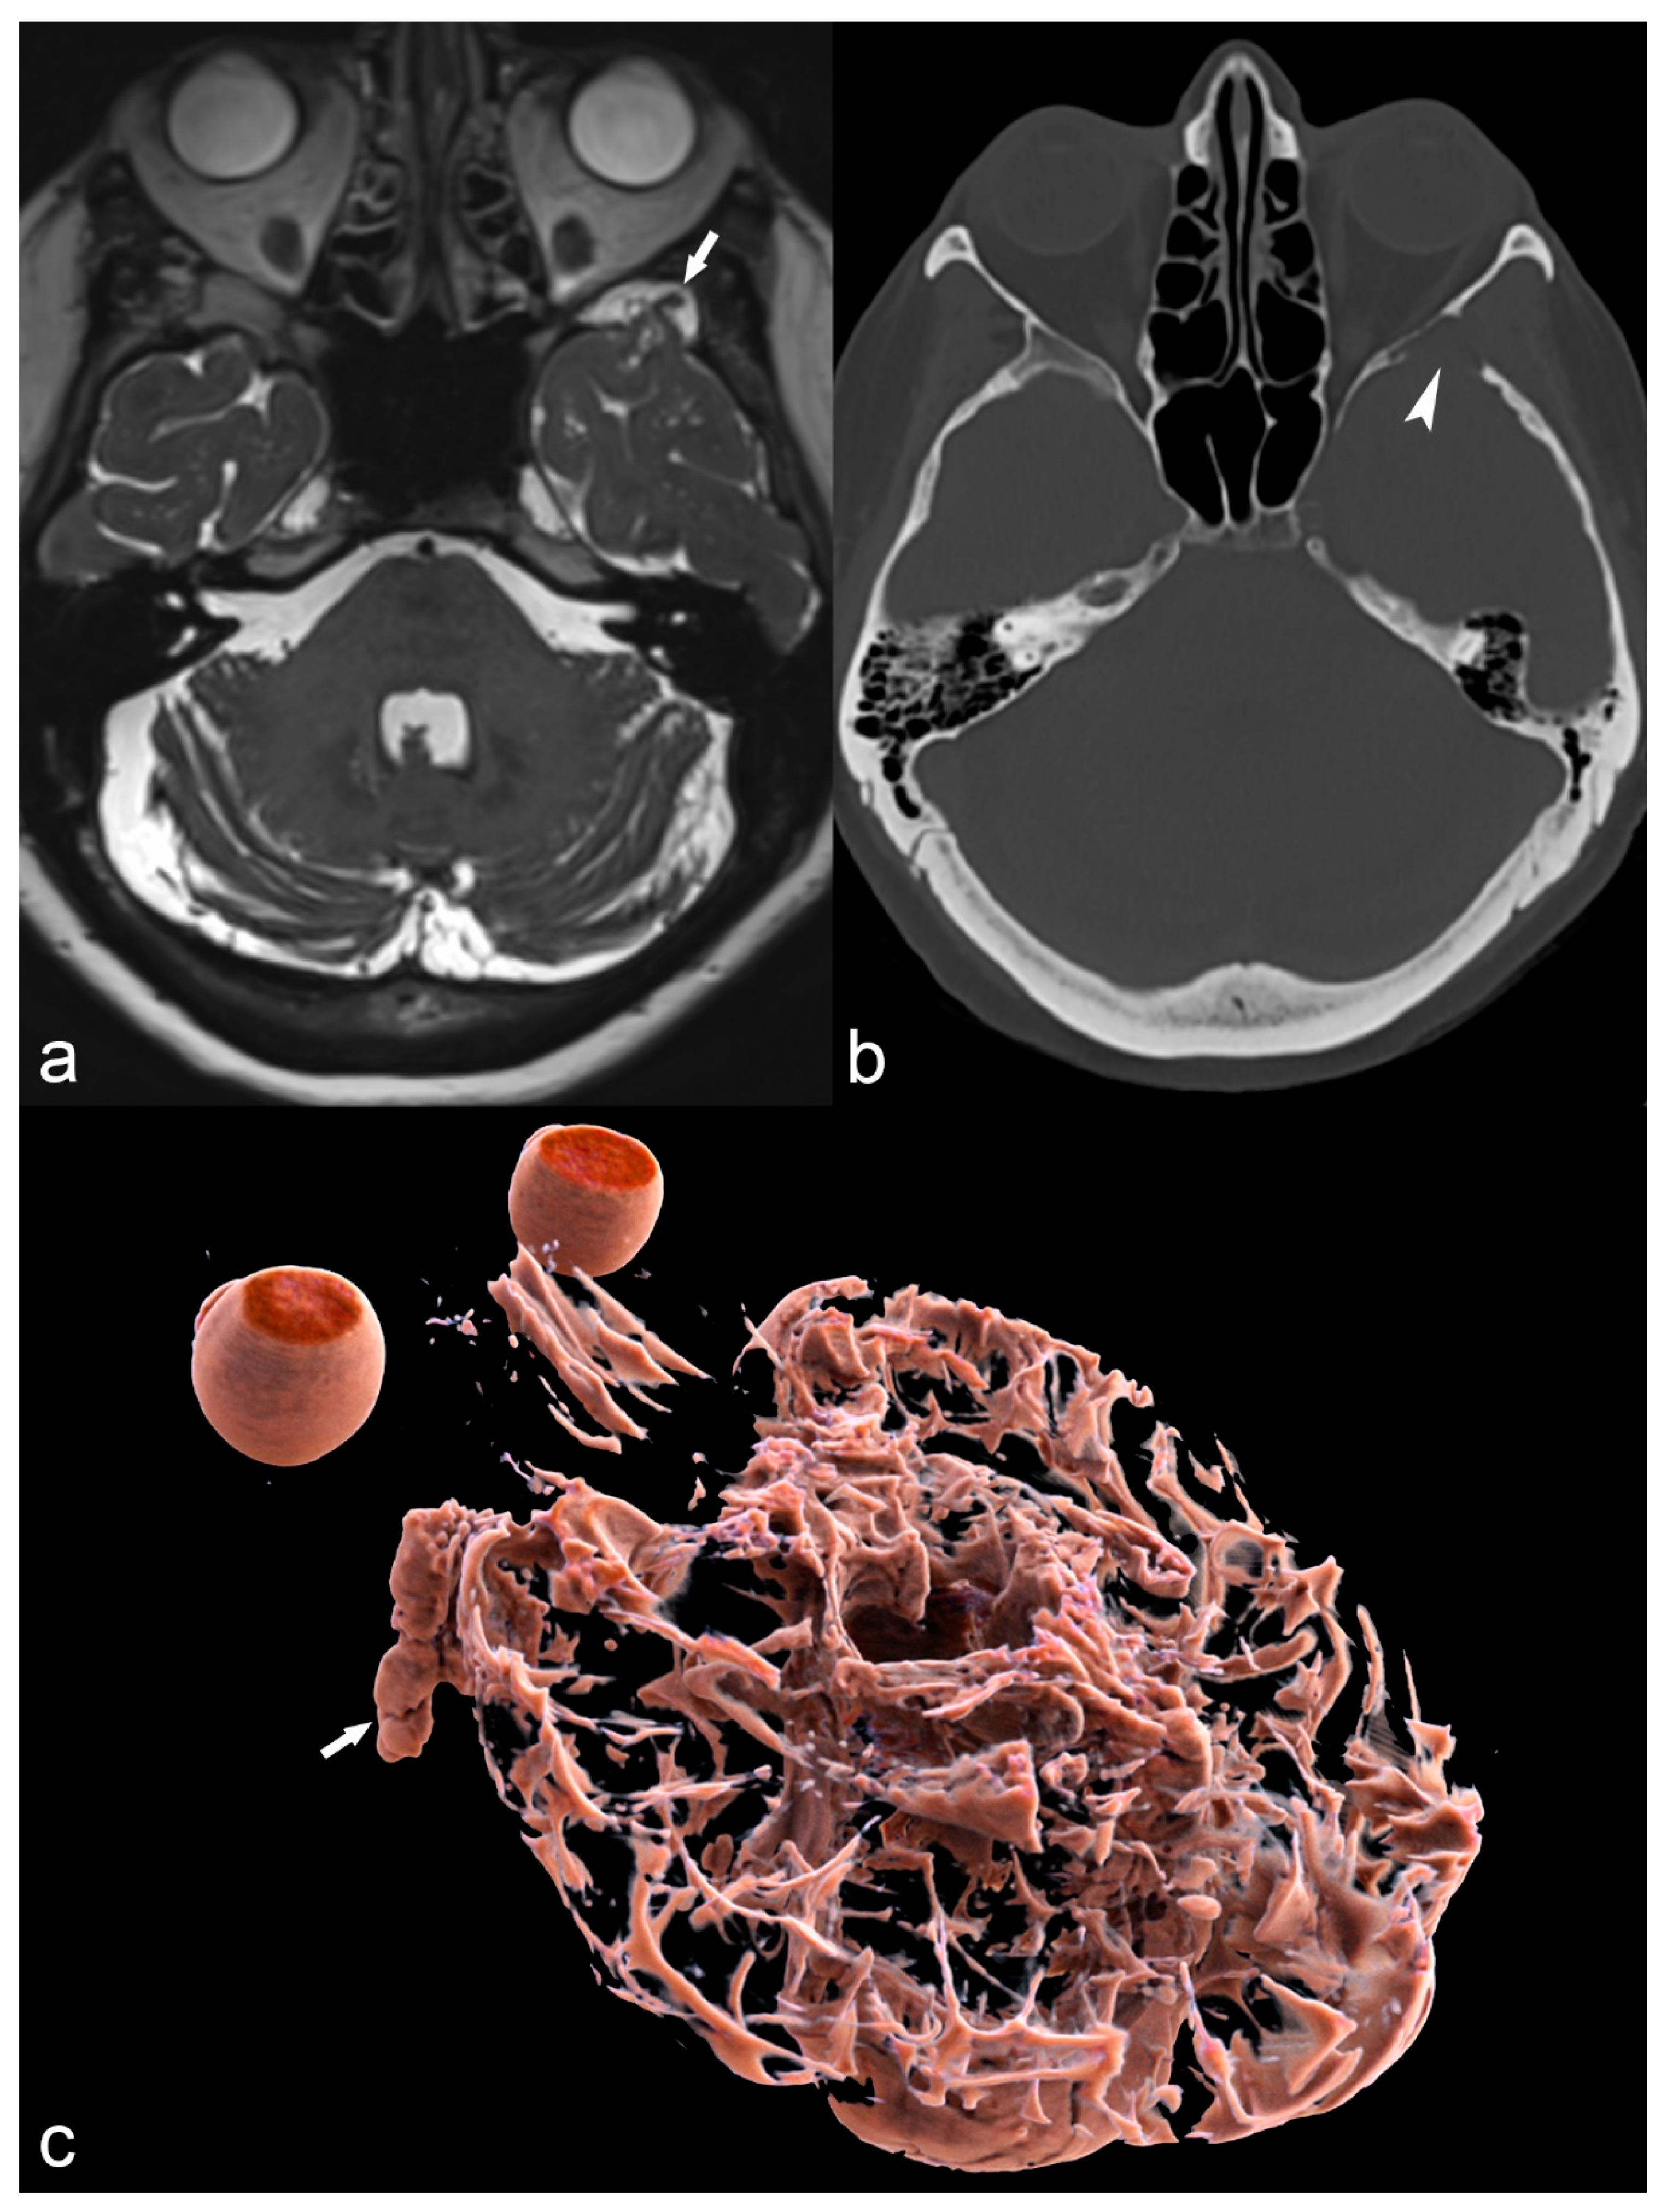

Figure 4.

36-year-old woman. The right hippocampus is smaller than the left (arrows) as seen on coronal T2WI (a), FLAIR (b) and MP2RAGE (c) and shows hyperintensity on T2WI and FLAIR. There is also flattening and loss of the normal undulations of the right hippocampus, suggestive of hippocampal sclerosis.